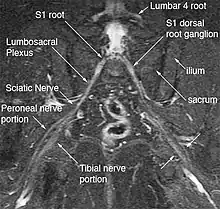

Bilateral magnetic resonance neurography of the sciatic nerves

The general workup involves excluding lumbar, pelvic, and hip pathologies, physical examination, magnetic resonance neurography (MRN) imaging, and diagnostic injections. The use of MRN and diagnostic injections are relatively new diagnostic tools that allow making precise diagnoses where standard diagnostic modalities has failed.[3] Nerve testing such as EMG and NCS can be done but there is little evidence it's helpful.[2] Differential diagnoses include pudendal nerve entrapment, ischiofemoral impingement, greater trochanter ischial impingement, and ischial tunnel syndrome.[1]

Magnetic resonance imaging (MRI) and magnetic resonance neurography (MRN) are the diagnostic procedures of choice for deep gluteal syndrome.[4][6][3] MRN provides additional information that MRI alone can't by visualizing structural properties of the sciatic nerve.[3] As an example of the diagnostic improvement of MRN, when MRI is used to assess piriformis muscle asymmetry, it has 46% sensitivity and 66% specificity for piriformis syndrome. When MRN is used and includes unilateral sciatic nerve hyperintensity at the sciatic notch, the sensitivity increases to 64% and the specificity increases to 93%.[3] MRN's advantage is in identifying anatomic nerve abnormalities by visualizing neural structures such as nerve diameter, nerve fascial edema, fascicular appearance, perifascicular and endoneural signal intensity.[5][6] Diffusion tensor imaging / Magnetic resonance tractography is expected to be another powerful clinical tool for diagnosis of deep gluteal syndrome because it can reveal additional physiological information about the nerves, but is still in the research phase.[6]